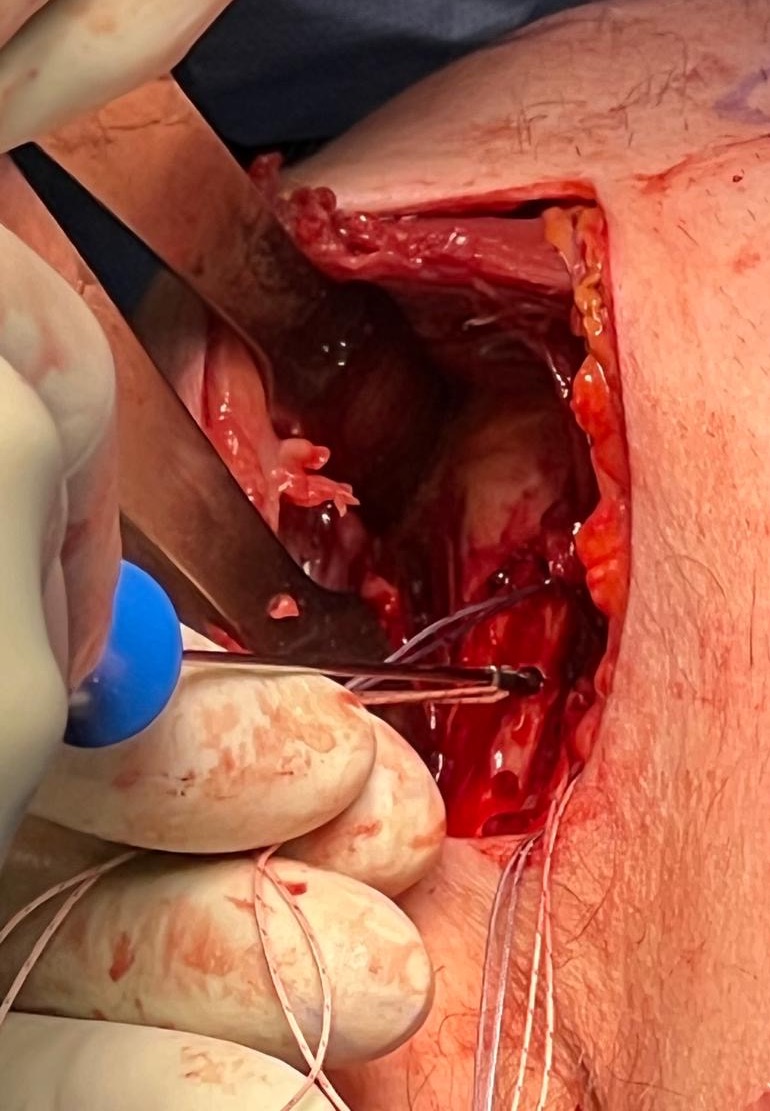

Axillary crease incision in right shoulder, with Kocher forceps on the torn pectoralis major tendon

Right shoulder, with Hohmann retractor exposing humerus